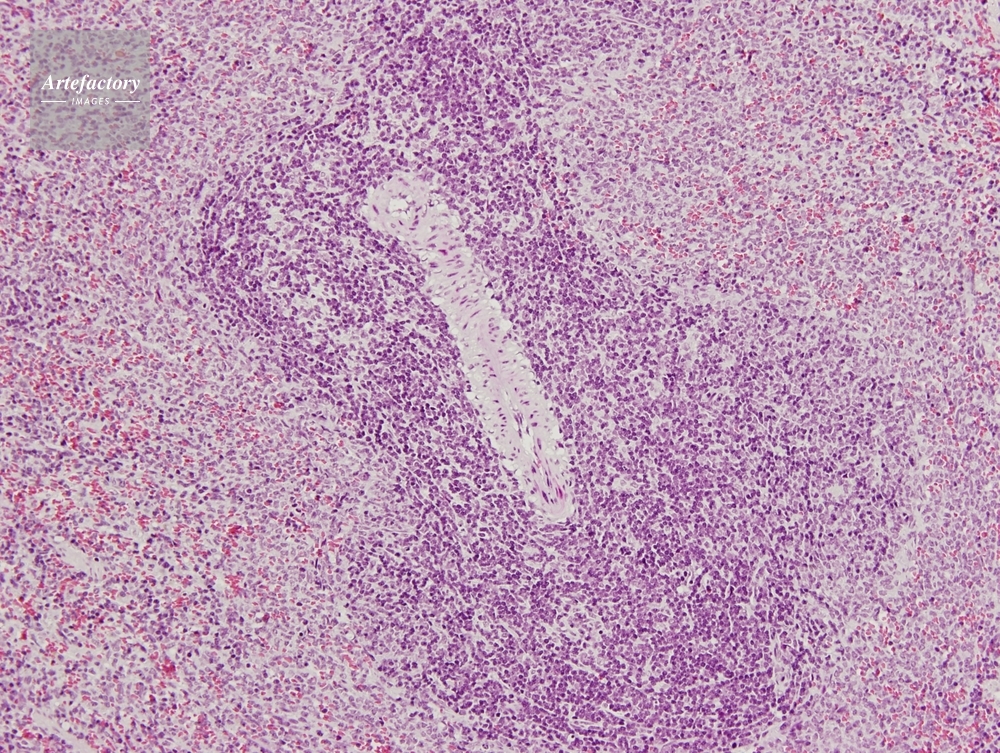

| 作品タイトル | マウス,脾臓 | モデルリリース | なし | |

| 作家 | OLYMPUS CORPORATION Technolab | プロパティリリース | なし | |

| ソース | ピクセル数 | 3455px × 2602px | ||

| 撮影地 | 印刷サイズ | 20.3cm × 15.3cm | ||

| 撮影年月日 | 2007/6/1 | データサイズ | 7.3MByte | |